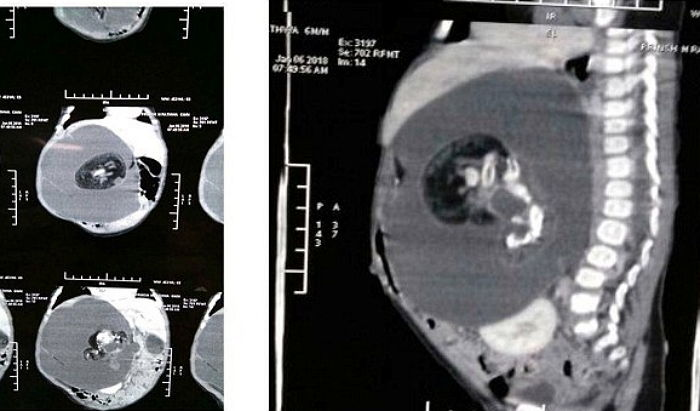

인도에서 태어난 프린사 라타바(Prinsa Rathava)는 생후 5개월 부터 혹이난 것처럼 배가 부풀어 올랐다.

바로 아이의 몸속에 또다른 태아가 있었던 것이다.

이것은 ‘태아 속 태아(Foetus In Fetu)’라는 병으로 쌍둥이 태아 한쪽이 엄마 배속에서 다른 태아의 몸으로 흡수되는 증상이다.

쌍둥이 태아는 라바타의 장과 신장 사이에 위치했으며, 수술을 통해 무사히 제거했다.

제거한 덩어리에는 형태를 알아보긴 힘들었지만 척추, 뇌 조직, 머리, 팔 눈 등을 가지고 있었다고 한다.